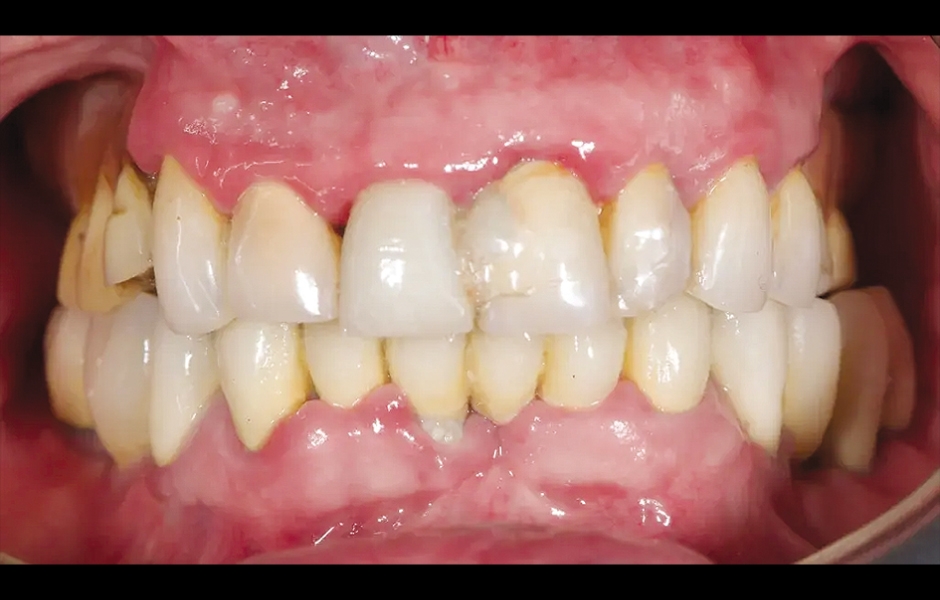

85letý částečně bezzubý pacient byl odeslán na naši kliniku k celkové rehabilitaci horní čelisti. Pacient byl v dobrém celkovém zdravotním stavu a nekuřák. Jeho hlavní stížnosti zahrnovaly obtíže při žvýkání, bolest v horní čelisti a občasný zápach z úst. Klinické a radiologické vyšetření odhalilo krátký fixní metalokeramický můstek nesený sedmi frontálními zuby horní čelisti. Protetická práce se uvolnila a čtyři z pilířových zubů byly strukturálně narušeny. Zbývající tři vykazovaly různé stupně kazivých lézí a parodontálních problémů. Byla stanovena diagnóza selhávající dentice (obr. 1 a 2).

Obr. 1: Výchozí situace, čelní pohled. (Všechny snímky: Dr. Marco Tallarico a kol.).

Obr. 11: Provizorní protetická práce s kovovou výztuhou in situ, čelní pohled.